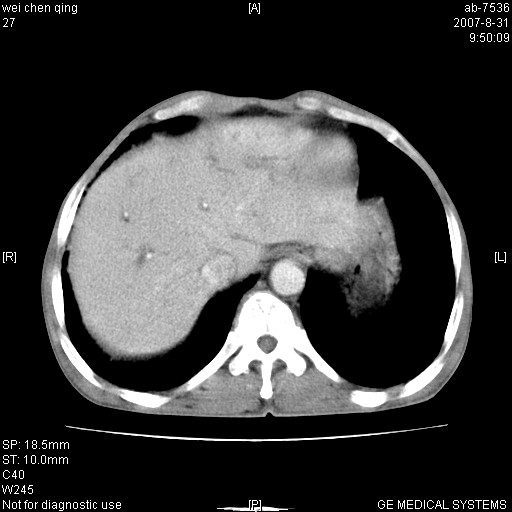

以下是引用zjzjr在2007-8-31 14:38:00的发言:[br]胰头癌伴肝内胆管扩张可能性大。

以下是引用zyyzzy在2007-8-31 14:34:00的发言:[br]该病人肝内胆管扩张,胆囊及胆总管未见明显扩张。在倒数第9层图像上可看到左右肝管结合部(肝总管)有软组织影,此处应薄层扫描。考虑肝总管占位(ca)、腹水。[br]